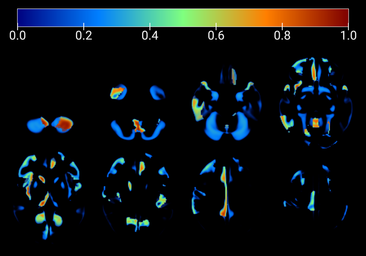

El encuentro internacional reunirá a científicos y técnicos de diferentes áreas de conocimiento: ingenieros de distintos campos –eléctricos, electrónicos, de sistemas, en computación, en biomedicina, telecomunicación, mecatrónica, telemática, software y cibernética–, pero también médicos, físicos y matemáticos. Una de sus principales áreas de trabajo es la Física Médica y, en particular, las técnicas de imagen aplicadas al diagnóstico y tratamiento de diversas alteraciones, entre ellas enfermedades neurodegenerativas como el alzhéimer y el párkinson o condiciones como el síndrome de Down y el autismo.

El congreso del IEEE abarca, en realidad, varias reuniones sectoriales: el Simposio de Ciencias Nucleares, sobre los últimos avances en tecnología y materiales de detectores y su implementación en física nuclear, astrofísica, aceleradores de partículas y seguridad nuclear; la Conferencia de Imágenes Médicas, con las últimas innovaciones sobre las aplicaciones de la radiación ionizante (radiografías, TACy TEP); y la Conferencia sobre Detectores de Semiconductores a Temperatura Ambiente, con aplicaciones en ámbitos tan diversos como la medicina, la seguridad, las astrofísica y la monitorización ambiental.